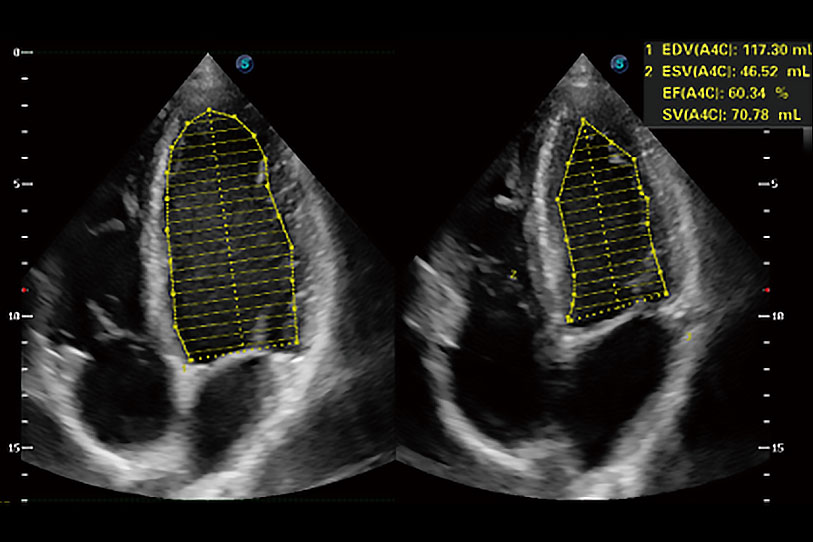

能夠基于左心室壁追蹤和辛普森法,自動(dòng)計(jì)算射血分?jǐn)?shù),支持多個(gè)可移動(dòng)點(diǎn)描跡,與手動(dòng)測(cè)量相比,極大節(jié)省了動(dòng)物醫(yī)生的時(shí)間和精力。

通過(guò)360度任意調(diào)節(jié)3條M型取樣線(xiàn),在同一心動(dòng)周期上觀(guān)察心臟不同位置的運(yùn)動(dòng)曲線(xiàn),得到準(zhǔn)確的心功能測(cè)量數(shù)據(jù),有效評(píng)估心肌運(yùn)動(dòng)及左心室功能。

當(dāng)心臟測(cè)量結(jié)果超出正常范圍時(shí),可實(shí)時(shí)預(yù)警提示動(dòng)物醫(yī)生,減少疾病漏診概率。